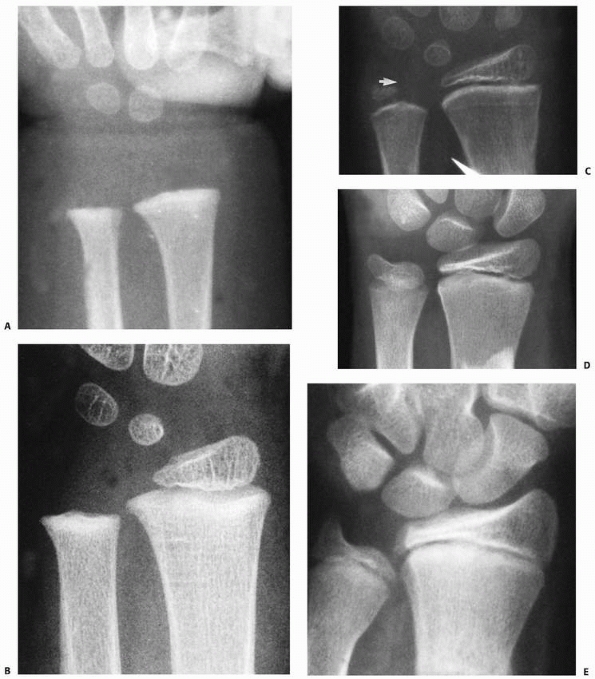

![]() |

FIGURE 9-2 Ossification of the distal radius. A. Preossification distal radius with transverse ossification in a 15-month-old boy. B. The triangular secondary ossification center of the distal radius in a 2-year-old girl. C. The initial ossification center of the styloid in this 7-year-old girl progresses radially (arrow). D. Extension of the ulnar ossification center into the styloid process of an 11-year-old. E. The styloid is fully ossified and the epiphyses have capped their relative metaphyses in this 13-year-old boy.